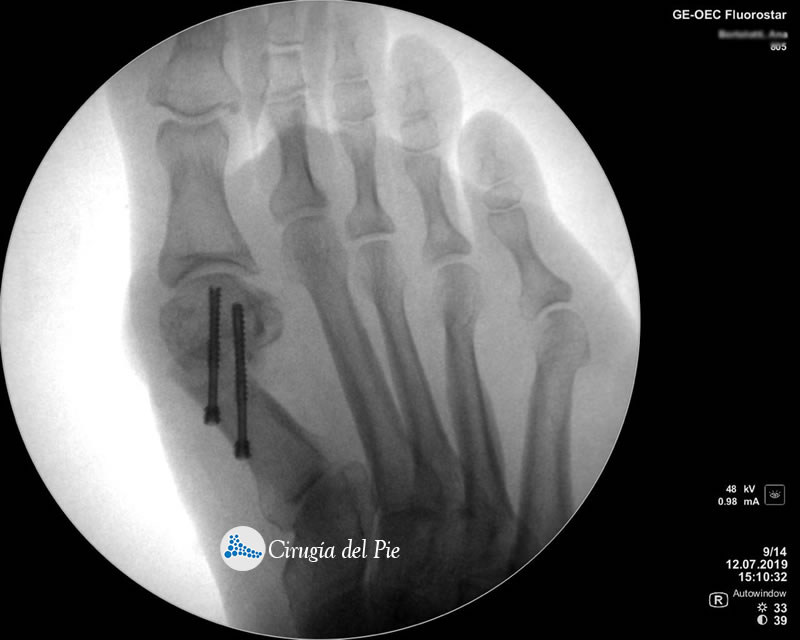

La cirugía Percutánea del pie, también conocida como cirugía MIS (Minimal Incision Surgery), permite realizar procedimientos quirúrgicos a través de pequeñas incisiones en la piel sin gran exposición ni trauma de tejidos.

De esta forma se disminuye el riesgo de complicaciones, como las lesiones de partes blandas, las infecciones y se obtienen menores tiempos operatorios, disminuyendo el dolor y acelerando la vuelta a la vida habitual.

Cirugia Percutanea Dr Masaragian